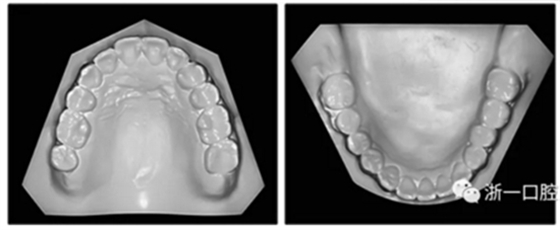

36歲;女性;尋求下頜左后方區(qū)域間隙管理的建議(圖1和圖2),通過治療獲得了良好的牙頜面效果(圖3和圖4)。她被診斷患有骨性I類和代償性牙性II類錯合畸形,并且上頜左側尖牙缺失(圖1和2)。大約七年前,由于不可修復的齲齒,拔除了下頜左側第一和第二磨牙(圖5)。37相鄰的第三磨牙向近中移動并傾斜入間隙,導致無牙頜間隙減小至約14 mm(圖2和圖5)。臨床和影像學評估顯示多發(fā)性齲損和在下頜右側567處有一不良的固定橋修復體(圖1和5)。此外,下頜左中切牙缺失,造成下頜中線向左側偏移約3 mm(圖1和圖2)?;颊咦栽V,她的右上第一前磨牙和左上尖牙在13歲時由其家庭牙醫(yī)拔除,因為它們被阻塞到頰側萌出(圖1)。上頜第二磨牙缺失(未知病因),并且相鄰的第三磨牙已經(jīng)轉移到第二磨牙間隙中。如補充材料所示,美國正畸學差異指數(shù)DI是28分。種植體部位(下頜左側和右側第一磨牙)由于復雜性得到額外4分(補充材料)。

圖2. 治療前牙齒模型